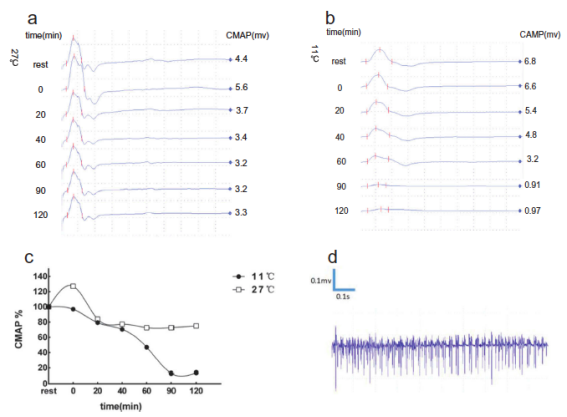

其中一个家系中部分成员基因分析考虑SCN4A基因(T704M)为其致病突变����,其长时程运动试验提示患者于常温所致先天性副肌强直合并高钾型周期性麻痹����。